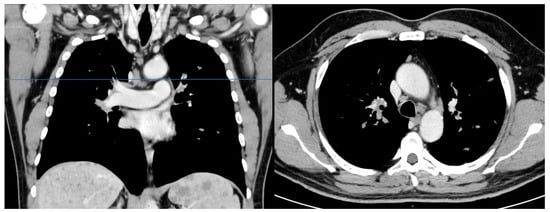

2. Case Presentation